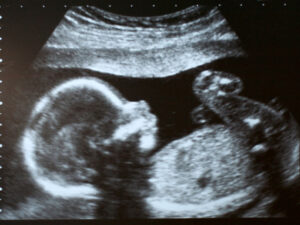

High-resolution ultrasound allows doctors to evaluate structure, movement, and circulation in greater detail. When an ultrasound shows changes in anatomy or development, providers can assess how those findings may affect your baby’s growth and overall health.

They may use additional imaging to monitor blood flow, placental function, or how well your baby is tolerating the pregnancy.